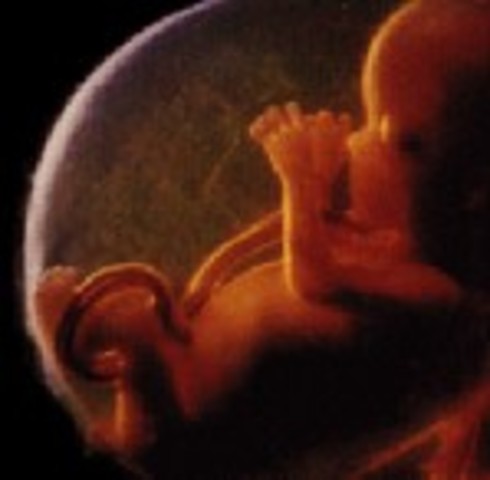

• Week 9: Fingers and Toes Form

Week 9: Fingers and Toes Form

Many more body parts are forming such as the tongue, the bones, eyelids, etc. The fingers and toes are the most defined. The baby is developing in a little bag of fluid which it is swimming around in.